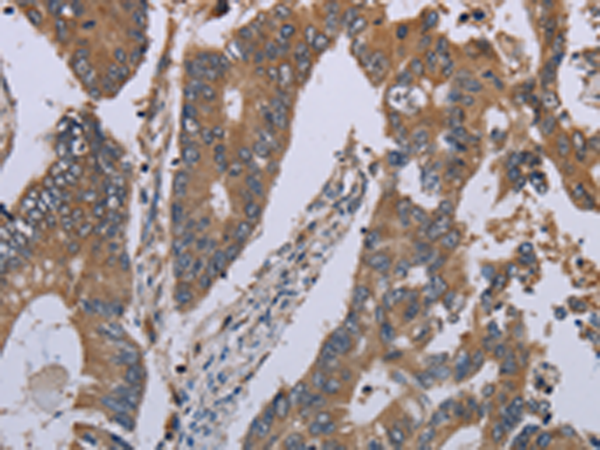

分类: 科研抗体货号: P05035别名: HCA1; DAMAGE应用: WB,IHC反应种属: Human